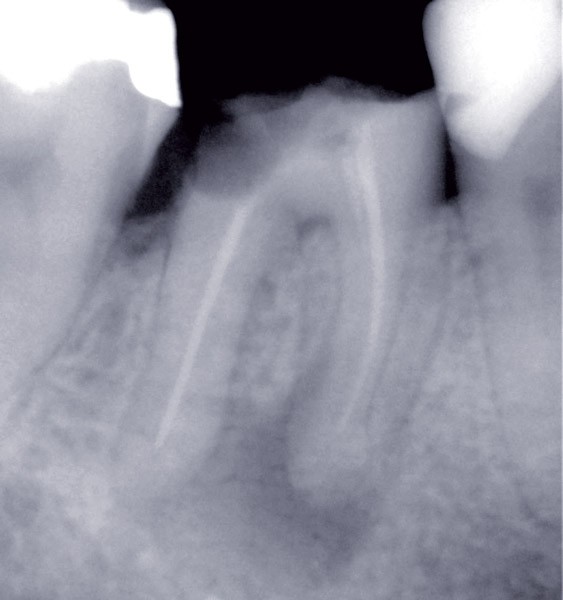

Dans un environnement parodontal sain, la chronologie des traitements conservateurs suite à la pathologie carieuse serait la suivante : le traitement endodontique de première intention, le retraitement endodontique et la chirurgie endodontique, voire l’amputation radiculaire. En cas d’échec, l’alternative implantaire pourra être envisagée (fig. 1).